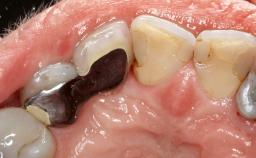

Despite anti-infective surgical treatment, some patients may experience recurrent infection and progressive bone loss requiring additional treatment. Removal of Implant Due to Recurrent Infection describes a conservative approach using an implant retrieval tool without the need for excessive bone removal or use of a trephine.

A 70-year-old female patient was referred by her general dentist to the periodontist for assessment and management of an infection associated with implant 36. The general dentist had noted suppuration on probing during examination.